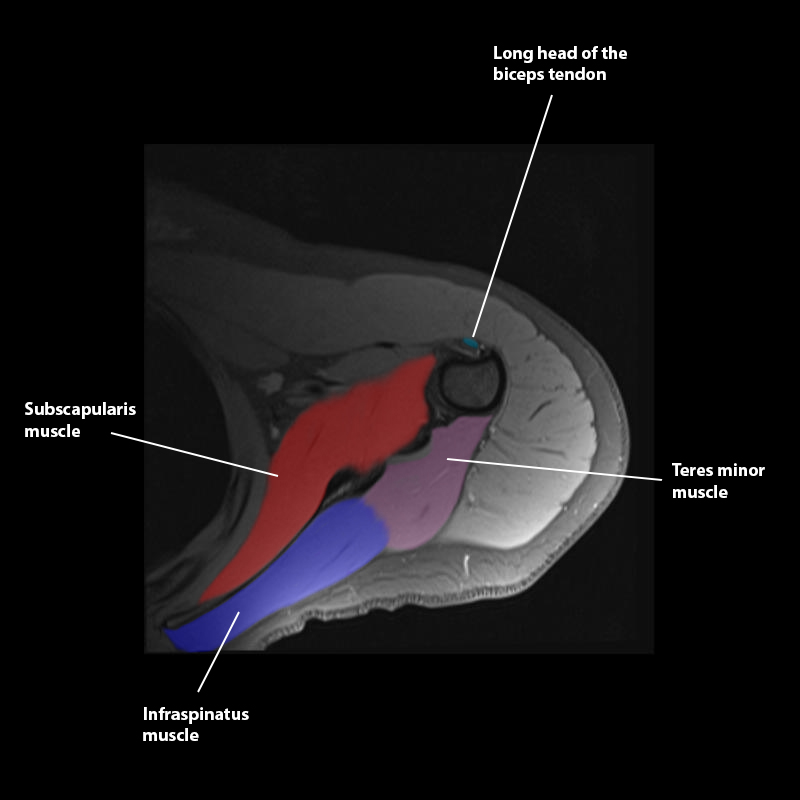

Shoulder MRI Anatomy